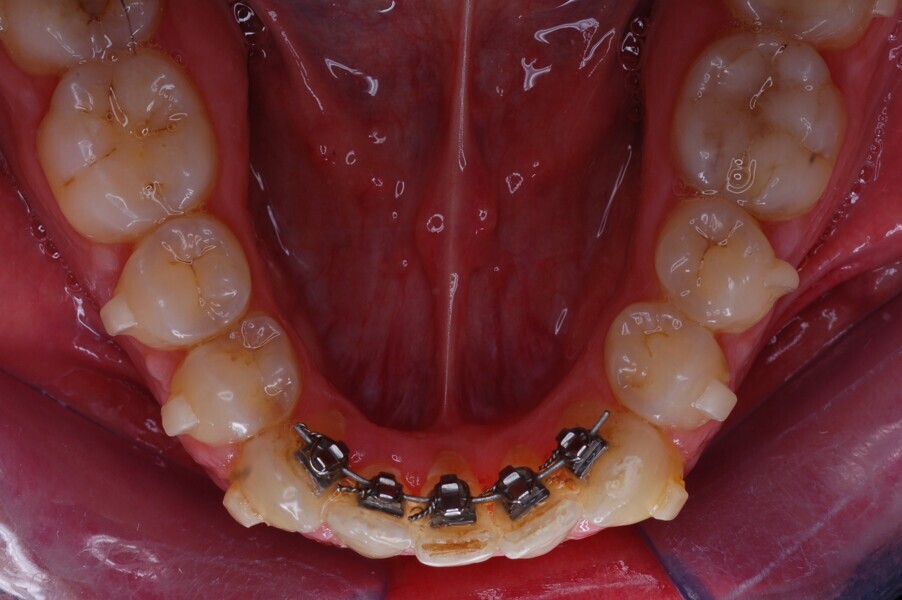

Fig. 37–44: Sequential intra-oral photographs illustrating progressive alignment of the mandibular arch.

Fig. 38.

Fig. 39.

Fig. 40.

Fig. 41.

Fig. 42.

Fig. 43.

Fig. 44.

The HAT technique requires the aligners to be adapted to the auxiliaries to create the necessary anchorage and allow tooth movement. The subsequent aligners were made to adapt to the lingual auxiliary to create the necessary anchorage so that only those teeth could be moved that required movement. This was done by creating 3D models used for thermoforming the aligners that resulted in the aligners having movement channels (spaces) incorporated into their design to allow teeth to move even when the aligners were placed over them. Teeth that were used as anchorage (the mandibular molars, premolars and canines) had no spaces so that the aligners fitted snuggly over them (Figs. 32 & 33). Rapid alignment was obtained in the mandibular anterior region in only nine weeks (Figs. 34–36). A prebent sectional 0.0175 × 0.0175 in. Gummetal wire was sent to us for the final stages of the alignment (Figs. 37–50).